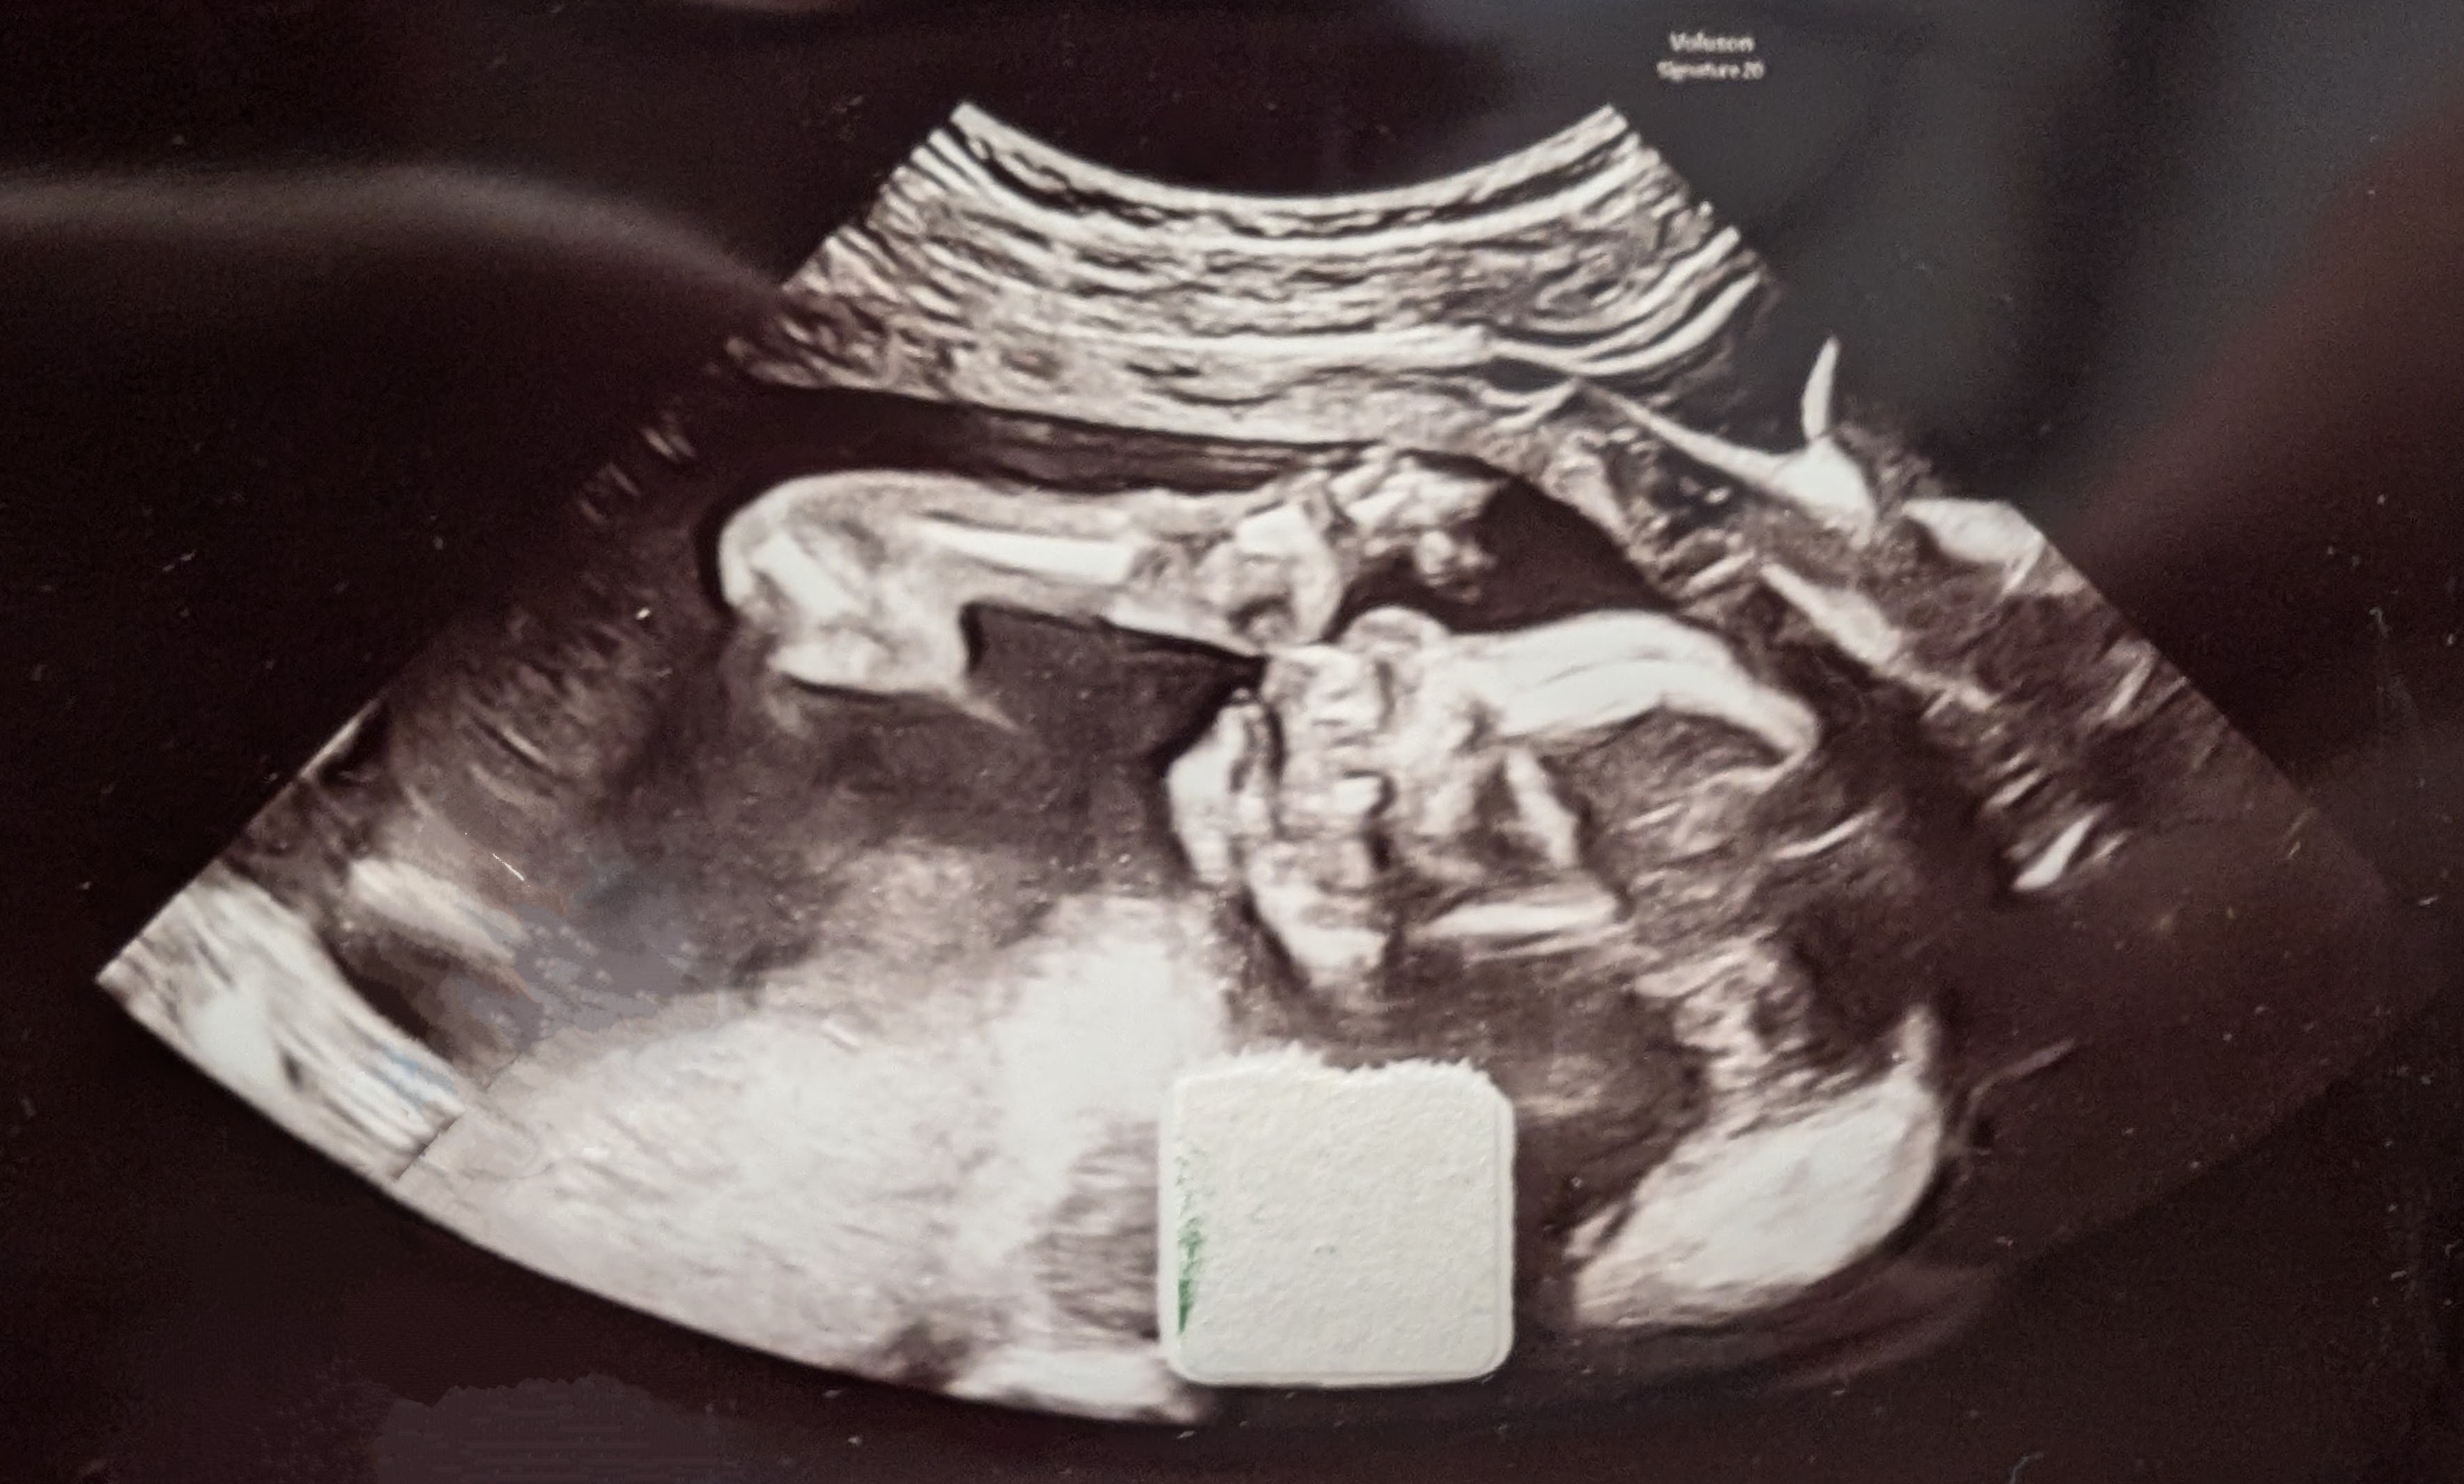

Second ultrasound!

He's getting bigger! Pemi is now 22cm (8.5in) and weighs 223g (half a pound).

He's a bit less tiny!